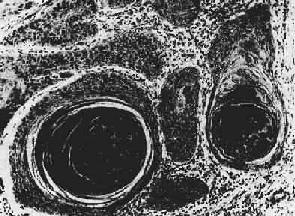

(1)腺(adenocarcinoma):较多见于胃肠、胆囊、子宫体等。细胞形成大小不等,形状不一、排列不规则的腺样结构,细胞常不规则地排列成多层,核大小不一,核分裂像多见(图7-13)。当腺伴有大量乳头状结构时称为乳头状腺;腺腔高度扩张呈囊状的腺称为囊腺;伴乳头性生长的囊腺称为乳头状囊腺

图7-13 腺(胃)

细胞排列紊乱,多层,形成大小不等、形状不规则的腺样结构,浸润于胃壁组织内